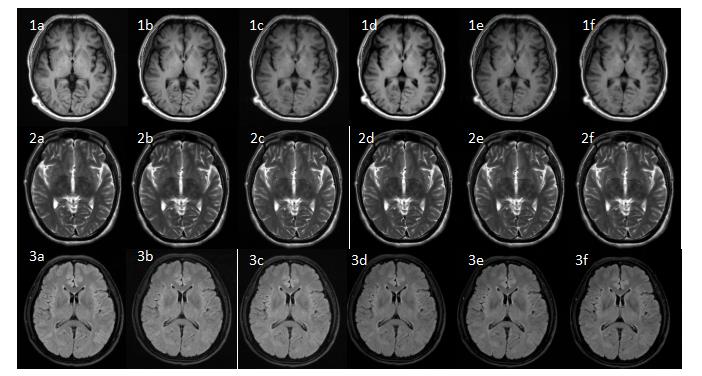

Figure 1 Male, 54-year-old. Panels 1a-1f are the axial T1-FLAIR images of the brain with PI AF=2, ACS AF=2, 2.5, 3, 3.5, and 4, respectively; Panels 2a-2f are the axial T2WI images of the brain with PI AF=2, ACS AF=2, 2.5, 3, 3.5, and 4, respectively. Panels 3a-3f are the axial T2-FLAIR images of the brain with PI AF=2, ACS AF=2, 2.5, 3, 3.5, and 4, respectively.